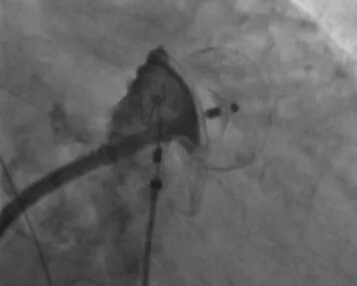

脉冲消融完成后进行经皮左心耳封堵术,交换鞘管,送入左心耳封堵器介入输送装置并沿尾端送入猪尾导管进行左心耳造影,测量后决定选LAAO-I28/38mm封堵器并封堵,造影及心腔内超声证实封堵器位置良好,符合“PAST”原则,成功。